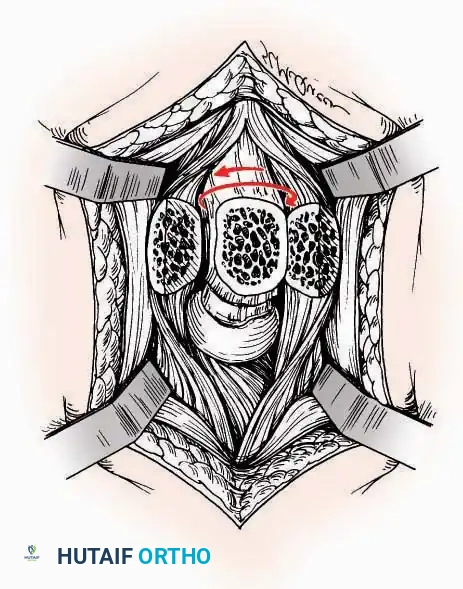

SURGICAL APPROACHES TO THE TARSUS AND ANKLE

Anterolateral Approach

The anterolateral approach is widely considered the "universal incision" for the foot and ankle. It provides unparalleled access to the ankle joint, the talus, and the majority of the tarsal articulations, while safely avoiding the major anterior neurovascular bundle. The only tarsal joints inaccessible via this route are the naviculocuneiform joints (specifically the medial and intermediate).

Indications: Total talectomy, triple arthrodesis, ankle arthrodesis, and open reduction of complex talar neck fractures.

Surgical Technique:

* Incision: Begin over the anterolateral aspect of the leg, medial to the fibula and 5 cm proximal to the ankle joint line. Carry it distally over the joint, crossing the anterolateral aspect of the talar body and the calcaneocuboid joint, terminating at the base of the fourth metatarsal.

* Superficial Dissection: Incise the superficial fascia and the superior and inferior extensor retinacula down to the periosteum of the tibia and the ankle joint capsule.

* Vascular Ligation: This trajectory usually requires the identification and ligation of the anterolateral malleolar and lateral tarsal arteries.

* Nerve Protection: Retract the skin edges carefully. Identify and protect the intermediate dorsal cutaneous branches of the superficial peroneal nerve (SPN), which frequently cross the distal aspect of this incision.

* Muscle Management: Identify the origin of the extensor digitorum brevis (EDB) muscle on the lateral calcaneus. Divide it in the direction of its fibers, or detach its origin entirely and reflect it distally to expose the subtalar and calcaneocuboid joints.

* Deep Exposure: Retract the extensor digitorum longus (EDL) tendons, the dorsalis pedis artery, and the deep peroneal nerve (DPN) medially. Incise the anterior ankle capsule to expose the tibiotalar joint.

* Tarsal Exposure: Expose the talonavicular joint by dissecting deep to the extensor tendons and incising its capsule transversely. Continue laterally through the capsule of the calcaneocuboid joint. By excising the fat pad within the sinus tarsi (lateral and inferior to the talar neck), the posterior facet of the subtalar joint is brought into direct view.